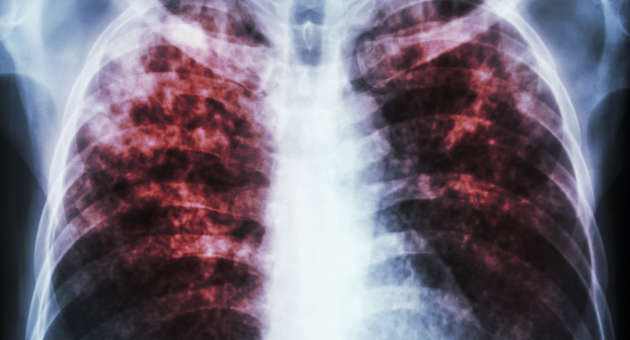

Asbestos Workers Are At Higher Risk For Covid-19 Complications COVID-19 is a respiratory illness and can cause extra complications for people with existing lung and breathing issues such as asbestos-related diseases. The Environmental Protection Agency (EPA) considers lung cancer, mesothelioma, and asbestosis to be the three significant health effects of asbestos exposure. All three are […]

People in Libby, Montana are More at Risk of Severe Symptoms When Contracting COVID-19 People in Libby, Montana are having a harder time with the COVID-19 pandemic compared to other parts of the country because they are also dealing with asbestos related diseases like asbestosis, mesothelioma, and lung cancer. People with these illnesses are more […]

Let’s All Work Together to Spread Mesothelioma Awareness Mesothelioma is a devastating cancer that is caused primarily by asbestos exposure. It is a terrible diagnosis to receive and not many people know what it is, which is why mesothelioma awareness is so important. Many people’s lives could be saved and could be improved if more […]